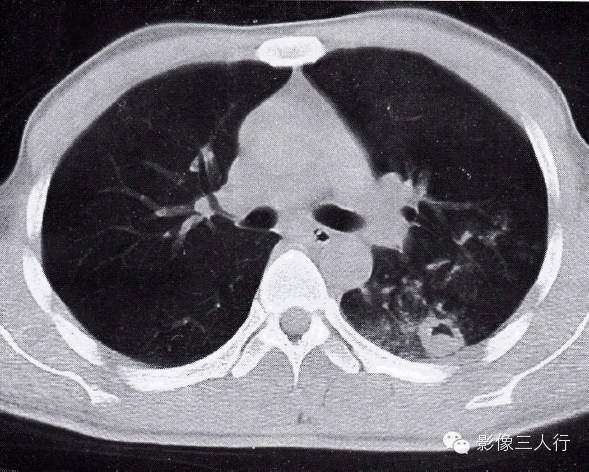

图2-85似肺炎的肺结核

双肺下叶大片状影,密度不均,内有支气管空气征,还有多发小点管腔影。边缘模糊,并有胸膜凹陷征